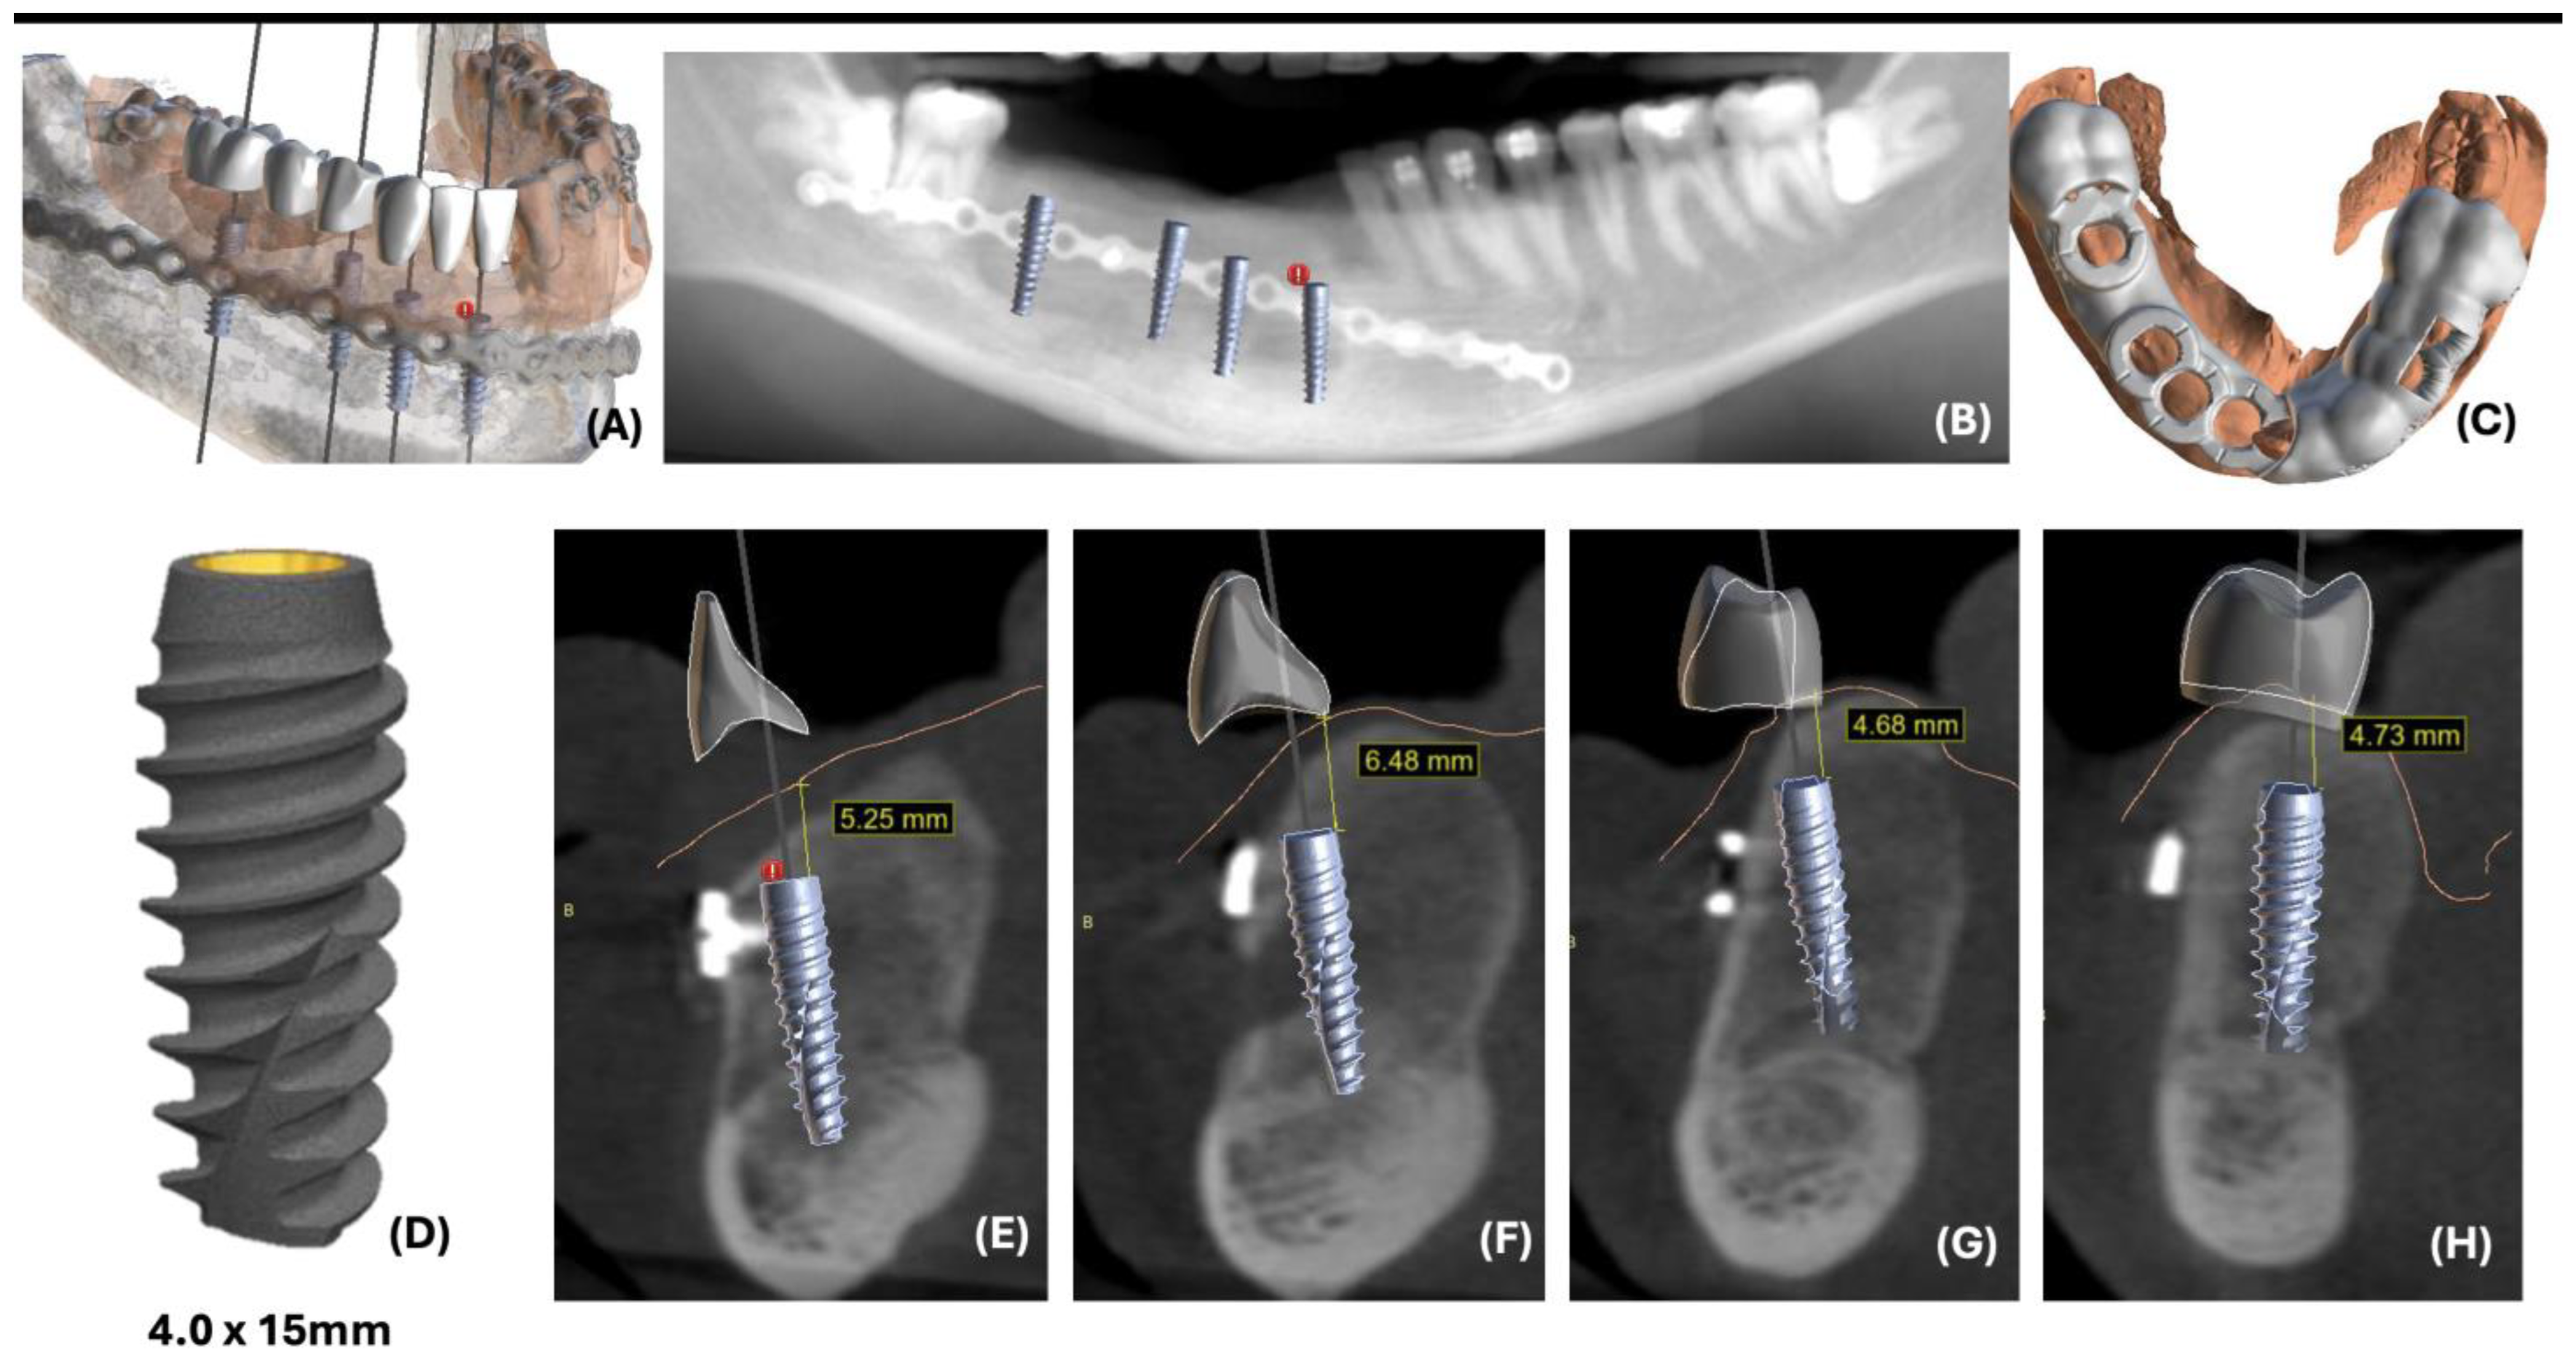

2.1. Case 1